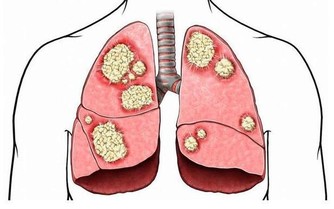

線索五:羅圈腿

預警:骨關節炎

整形外科專家認為這種步態通常是由於膝關節炎造成的,人群中有高達85%的人或多或少患有這種骨科疾病,通常是由於年齡增長造成骨骼損耗引起的,如果嚴重,可通過支架糾正。